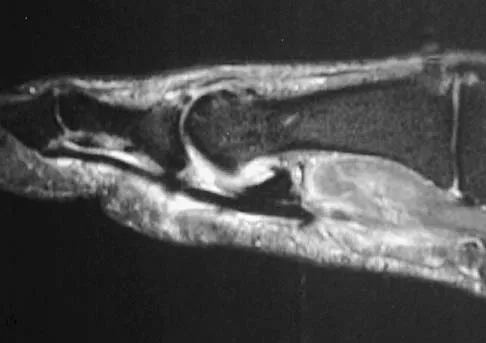

A 16-year-old boy has had thigh pain for the past several months. He denies any history of trauma. Examination reveals a large, deeply fixed, soft-tissue mass in the thigh. Laboratory results show an elevated erythrocyte sedimentation rate (ESR) and leukocytosis. A plain radiograph and MRI scan are shown in Figures 1a and 1b. Biopsy specimens are shown in Figures 1c and 1d. What is the most likely diagnosis?